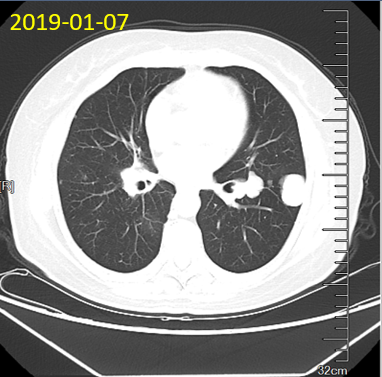

2019-01-07复查胸部CT提示肺部病灶明显增大、增多,但患者生活质量良好,拒绝再次化疗,要求继续瑞戈非尼治疗;

2019-03-21、2019-06-19 复查胸部CT提示肺部病灶稍增大,疗效评价:SD;